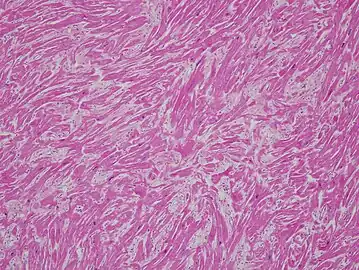

a-c) Histological abnormalities in cardiomyopathy -

Stained microscopic section of heart muscle in hypertrophic cardiomyopathy -